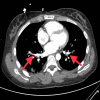

Figure 2

Figure 2. Large area of consolidation in the right lower lobe with patchy airspace opacification in the left lower lobe

Figure 3

Figure 3. Small amount of pulmonary artery embolus in the lobar branch of the left lower lobe and in the right lower lobe